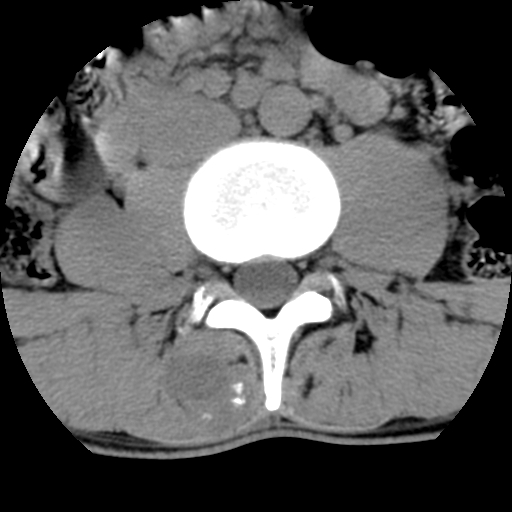

男,腰背痛

本人诊断1tb2包虫,请会诊

1)右侧竖脊肌稍低密度肿块伴钙化(性质待定),不排除肿瘤可能;建议行进一步检查。2)腰椎间盘突出。

1.右侧竖脊肌软组织肿块伴团块状钙化,首先考虑血管瘤可能性大;建议行进一步检查;2。腰椎间盘突出。